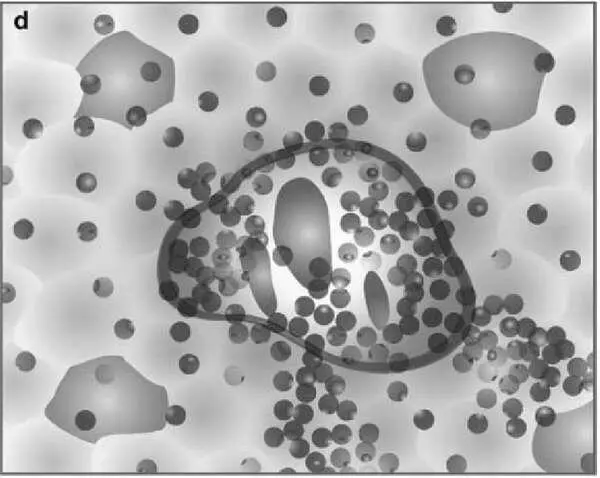

На рисунке представлена последовательная схема некротических и воспалительных изменений в печени при хроническом гепатите (по Batts–Ludwig). Воспалительная инфильтрация портальных трактов является обязательным компонентом поражения печени при гепатите и оценивается во всех системах. В оценочной шкале Баттс–Людвига выраженность гистологической активности гепатита градируется от 1 до 3 (a, b, c). На рисунке d представлена схема сливных некрозов в виде мостовидных некрозов, которые свидетельствуют о выраженной степени активности гепатита и соответствуют 4 стадии активности по системе Баттс–Людвига (Batts KP, Ludwig J. Chronic hepatitis. An update on terminology and reporting. Am J Surg Pathol 1995;19:1409–1417.15).